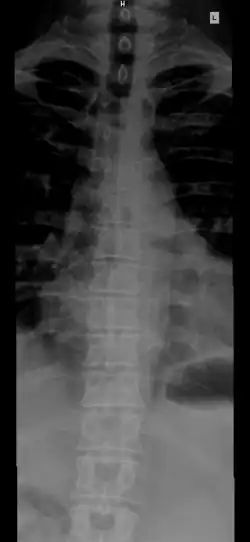

The number of vertebrae in a region can vary but overall the number remains the same. In a human spinal column, there are normally 33 vertebrae.[3] The upper 24 pre-sacral vertebrae are articulating and separated from each other by intervertebral discs, and the lower nine are fused in adults, five in the sacrum and four in the coccyx, or tailbone. The articulating vertebrae are named according to their region of the spine.

From top to bottom, there are 7 cervical vertebrae, 12 thoracic vertebrae and 5 lumbar vertebrae. The number of those in the cervical region, however, is only rarely changed,[4] while that in the coccygeal region varies most.[5] Excluding rare deviations, the total number of vertebrae ranges from 32 to 35.[6] In about 10% of people, both the total number of pre-sacral vertebrae and the number of vertebrae in individual parts of the spine can vary.[7][8][9] The most frequent deviations are: 11 (rarely 13) thoracic vertebrae, 4 or 6 lumbar vertebrae, 3 or 5 coccygeal vertebrae (rarely up to 7).[9]

The vertebrae in the human vertebral column is divided into different body regions, which correspond to the curvatures of the vertebral column. The articulating vertebrae are named according to their region of the spine. Vertebrae in these regions are essentially alike, with minor variation. These regions are called the cervical spine, thoracic spine, lumbar spine, sacrum, and coccyx. There are seven cervical vertebrae, twelve thoracic vertebrae, and five lumbar vertebrae.

The number of vertebrae in a region can vary but overall the number remains the same. The number of those in the cervical region, however, is only rarely changed.[4] The vertebrae of the cervical, thoracic, and lumbar spines are independent bones and generally quite similar. The vertebrae of the sacrum and coccyx are usually fused and unable to move independently. Two special vertebrae are the atlas and axis, on which the head rests.

From top to bottom, the vertebrae are:

- Cervical spine (neck): 7 vertebrae (C1–C7)

- Thoracic spine (chest/upper back): 12 vertebrae (T1–T12)

- Lumbar spine (lower back): 5 vertebrae (L1–L5)

- Sacrum (pelvis region): 5 (fused) vertebrae (S1–S5)

- Coccyx (tailbone): 4 (3–5, fused) vertebrae